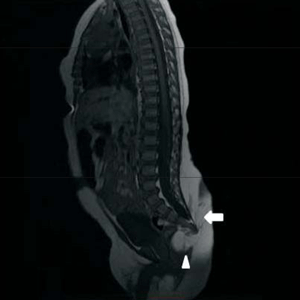

Con el resultado de la ecografía se solicita resonancia magnética de región lumbosacra para completar valoración. En ella se destaca: malformación sacrocoxígea con canal raquídeo con su extremo caudal llegando a S4.

Se aprecia quiste intrarraquídeo a la altura de S1 y S2 y un nódulo en tejido adiposo que se introduce en la pelvis por debajo del extremo del sacro y en topografía postero y laterorrectal izquierda.

El recto impresiona desplazado hacia adelante y algo comprimido.

No se observa lipoma penetrando en el canal (Figura 3).

Figura 3: Resonancia magnética. Flecha: extensión del canal raquídeo. Punta de flecha: lipoma pélvico.